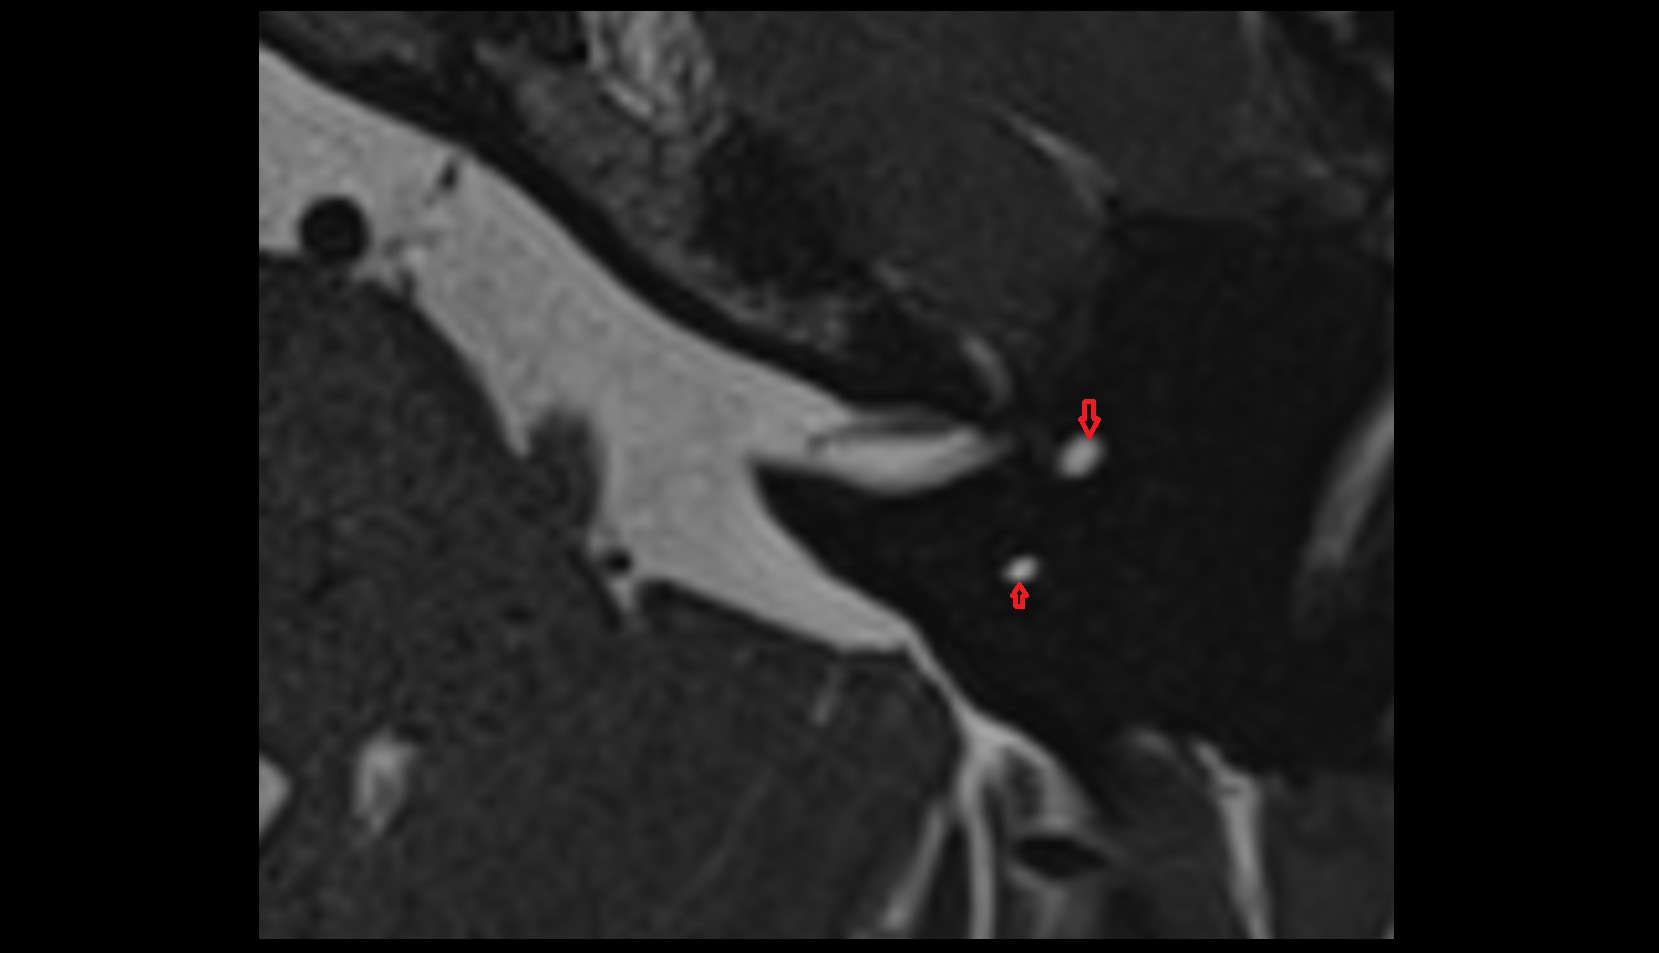

- Temporomandibular joint

- Articular disc of temporomandibular joint

- Articular eminence

- Mandibular condyle

- Mandibular fossa